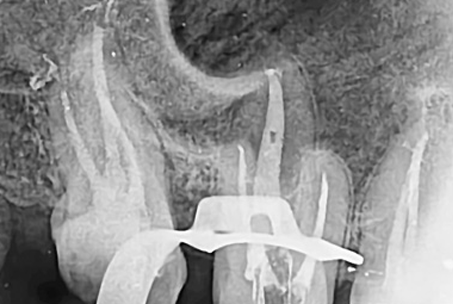

The images above show actual cases treated at SMILE FACE DENTAL CLINIC.

To a non-specialist, they may appear to be ordinary X-rays, but dentists can instantly recognize them.

They can appreciate both the complexity of the treatment and the care and precision involved.